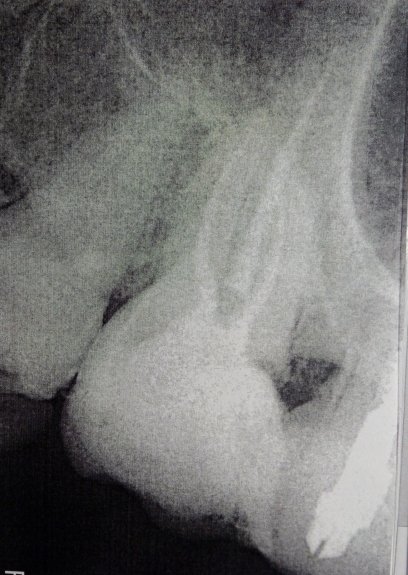

Врач поставил коронку на седьмой левый верхний зуб, несколько раз пришлось менять. В один из приемов он поставил ее на незакрытые каналы, началось воспаление. С ним очень сложно было иметь дело, я пошла к другому доктору с тем, чтобы он ее снял и почистил каналы. Со временем он их закрыл, но как выяснилось ― палатальный на 3 мм ниже и соседний ― на полтора. Есть рентген. Пожалуйста, посмотрите, можно ли ставить коронку при таком состоянии, как сейчас?

Уже пять лет эта мука продолжается, каналы загибаются внутрь в непройденных местах и не вскрыты даже, как мне кажется. На снимке это не выглядит как пустоты. Я ничего в этом не понимаю. Ковырять опять иголкой на 2,5 см в челюсть, очевидно, мучительно. Воспаления там нет. Боли в зубе никакой не ощущается ни при жевании, ни при кусании, вообще. Больше беспокоят ощущения во всей левой челюсти сверху, место заметно потревожено и отдает по лицевому нерву к носу, вдоль головы и к виску. Может, это просто пройдет со временем. Конечно, по новой вскрывать и перепломбировывать каналы не хочется, это такая пытка.

Пожалуйста, посмотрите, насколько потенциально опасно ставить коронку на зуб в таком состоянии, как сейчас. И что делать с левым виском? На фото это средний зуб, восьмерка справа от него.

6 и 7 зубы необходимо перелечить, после поставить культевые вкладки и коронки. На верхушках обоих зубов имеется обширный воспалительный процесс.